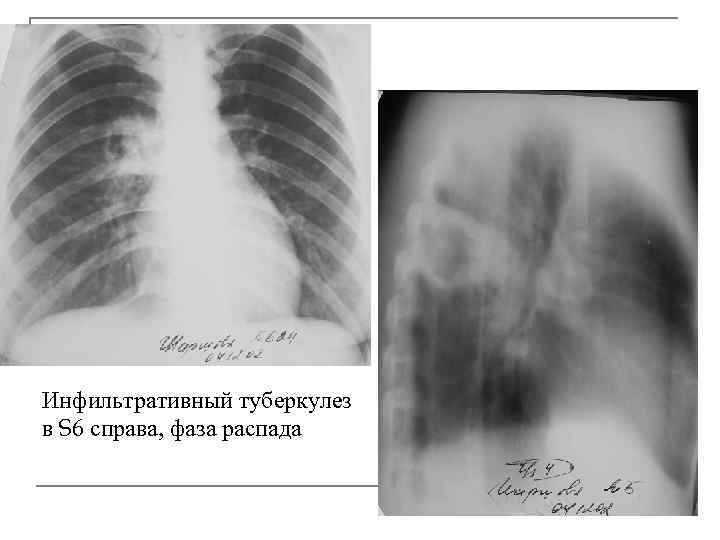

Симптомы и лечение инфильтративного туберкулеза легких

Раздел: Снимки-откровения